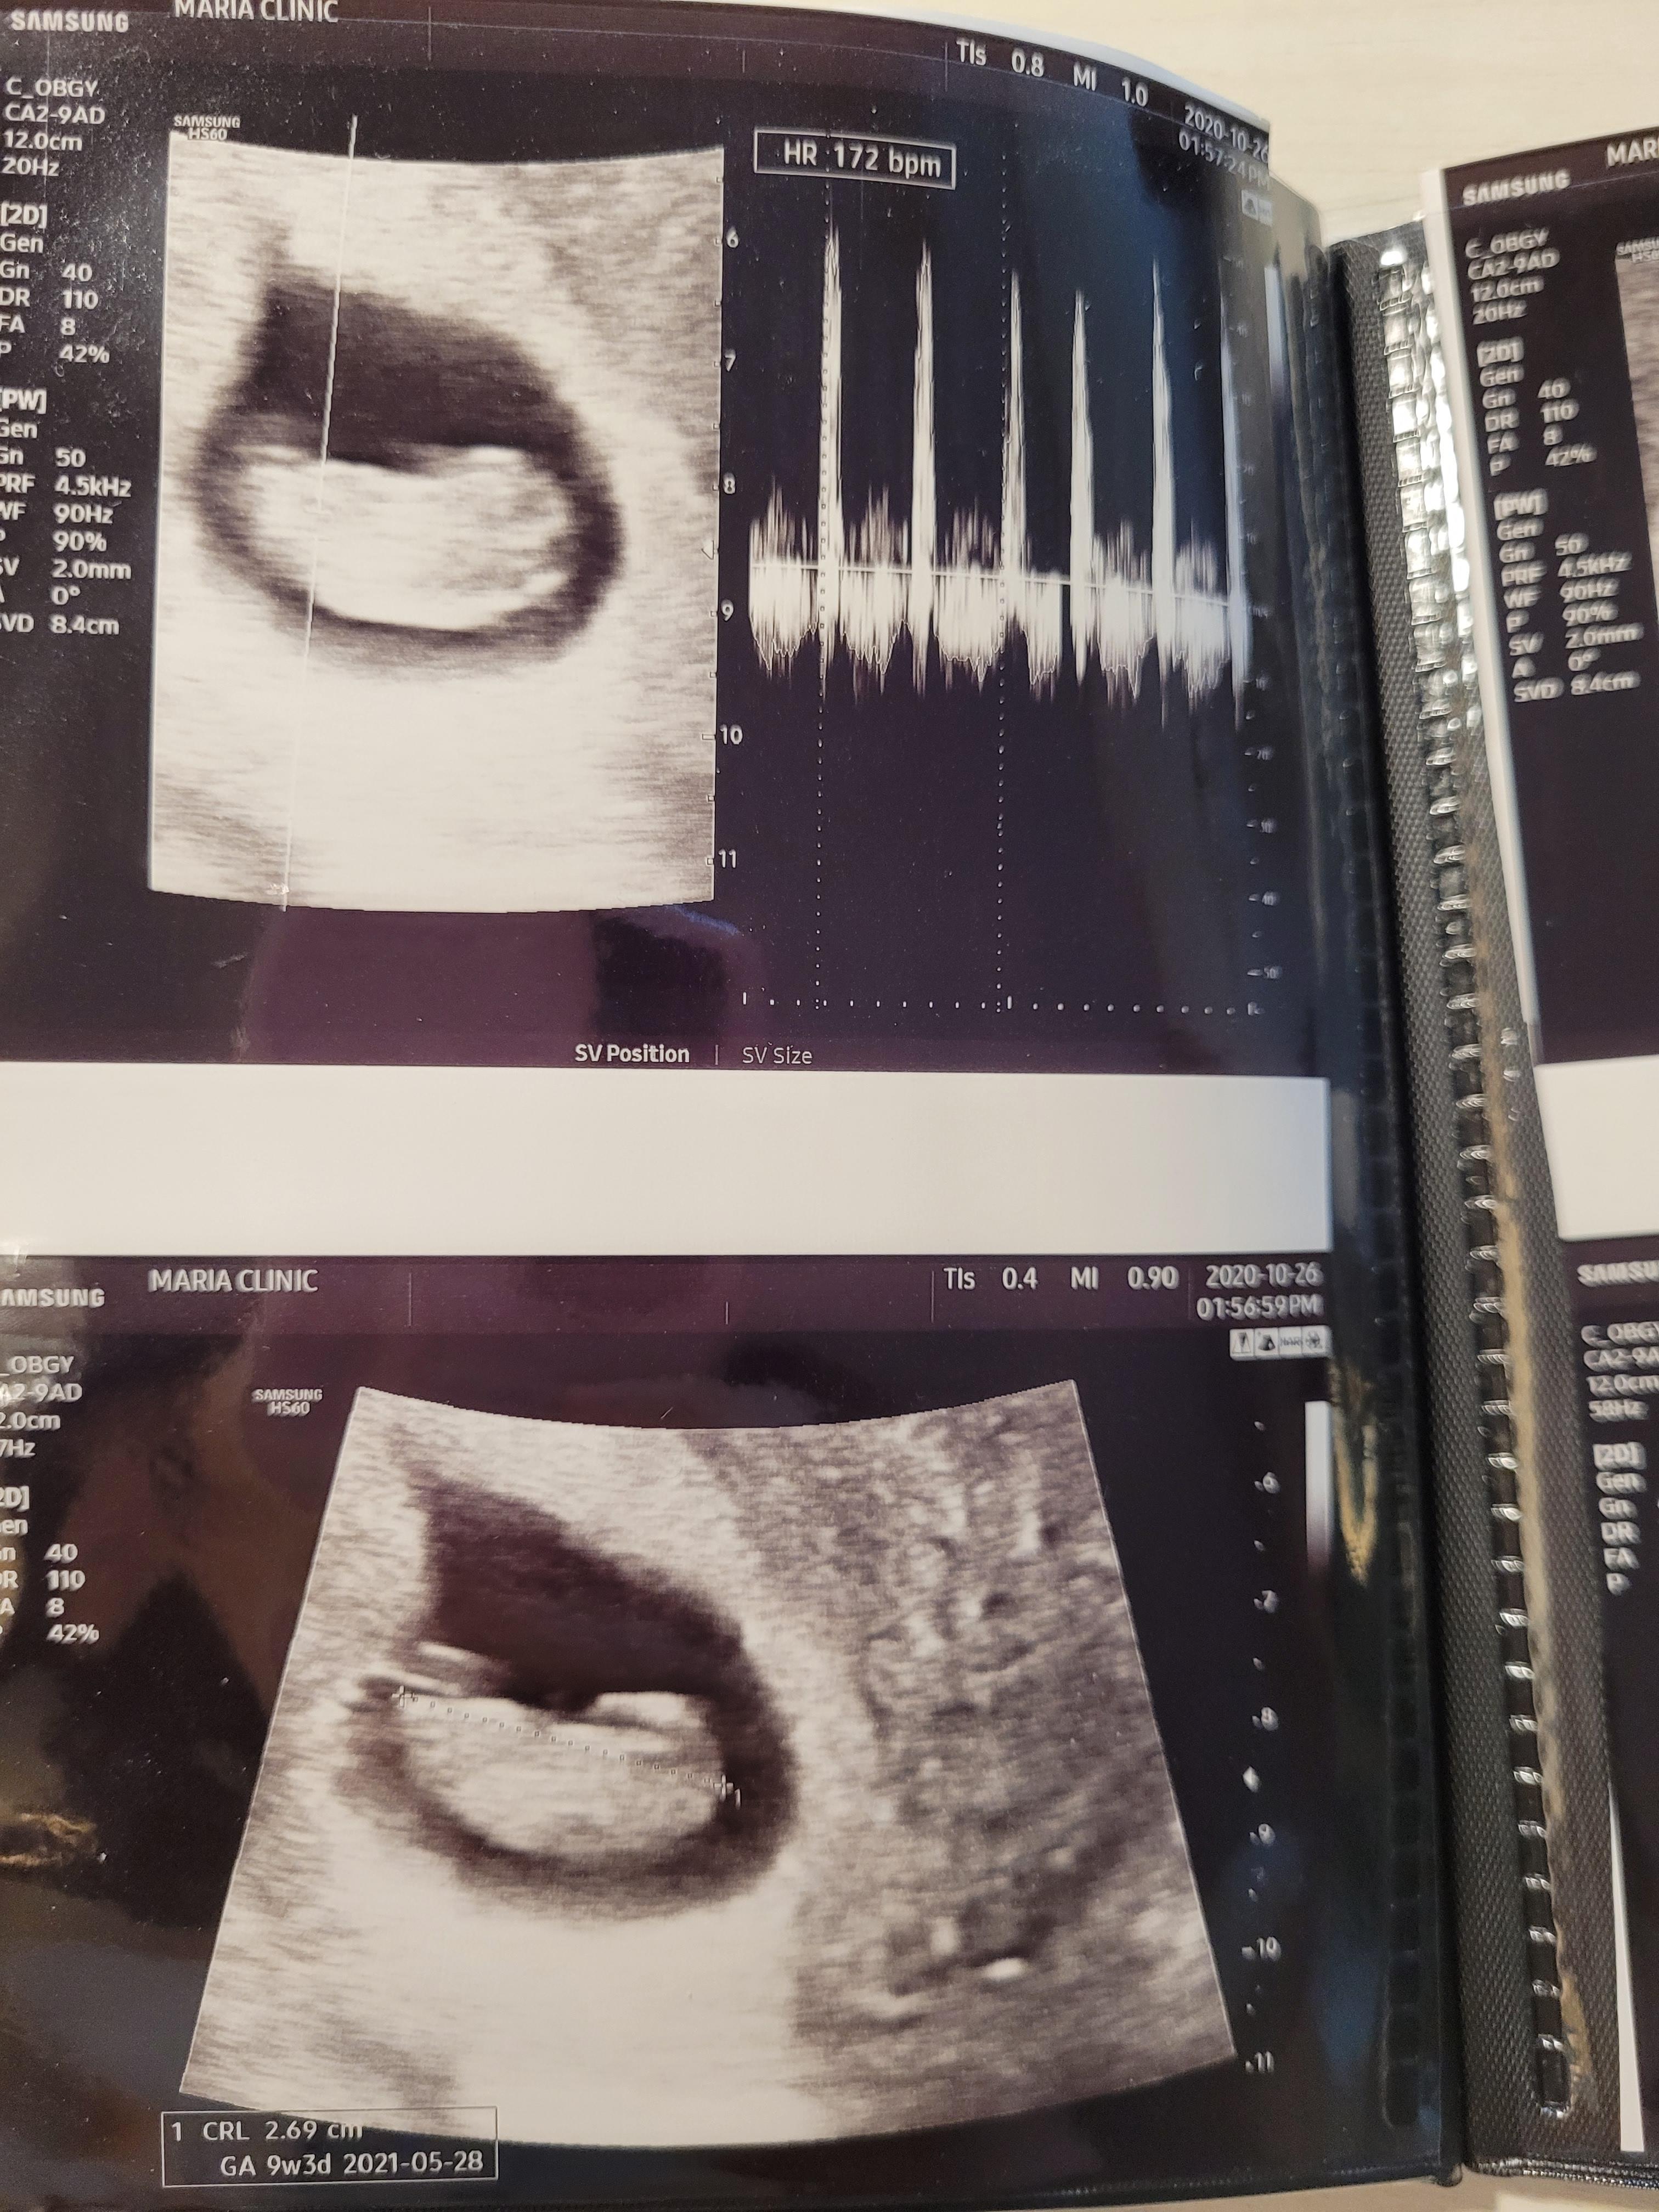

임신 9주 0일 평촌마리아 검진

임신 9주차에 접어들었어요.

9주 0일 진료에요. 8주보다 아가가 1cm정도 컸네요. 아기도 잘 컸고, 심장박동수도 잘 뛰더라고요.